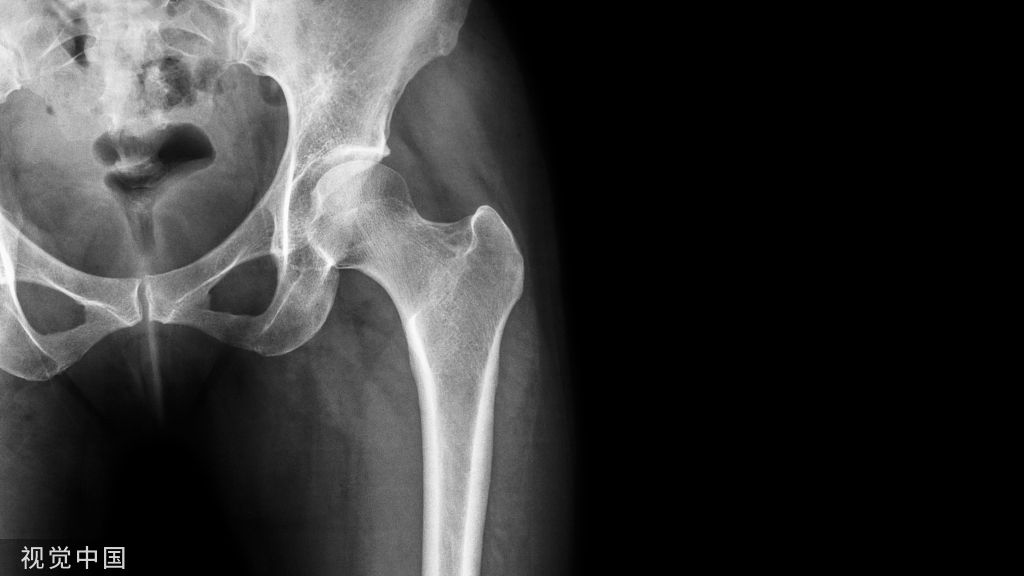

髋关节退行性骨关节病

又称髋关节骨性关节炎,是以髋关节软骨退变和其边缘骨质增生为特征的非炎症性疾病,可继发于其它疾病。

影像诊断:1、X线:早期髋臼上缘密度增高,股骨头凹边缘微小骨赘形成,继续发展可见较大骨赘,关节间隙上外侧非对称性狭窄,关节面边缘骨质增厚、关节面下假囊肿形成,重者出现股骨头半脱位,关节一般无骨质疏松,软组织无明显萎缩。(首选检查)

2、CT:髋臼前后唇、股骨头及髋臼窝边缘骨质增生,骨性关节面不规则硬化,关节间隙狭窄,承重面下出现假囊肿,关节腔可见积液及游离体。

3、MRI:早期软骨内显示条状或不规则低信号带,软骨局部变薄,表面不光整;继而外缘出现骨质增生,关节面软骨下出现骨硬化带;进一步发展出现软骨下假囊肿,关节腔游离体,关节腔狭窄,甚或半脱位。